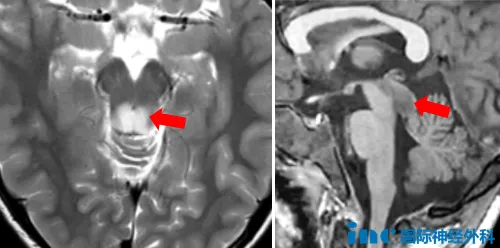

异常信号位于脑干中脑背侧,疑似胶质瘤。此时一家人才后知后觉,原来孩子的头痛、呕吐并不是单纯的感冒这么简单……为了进一步诊断,一家人带着晓飞来到北京,CT以及MRI再次确认中脑顶盖占位,大小约181214mm,边界不清,医生怀疑为低级别胶质瘤。

然而,由于肿瘤位置特殊,毗邻多个重要脑组织,包括中脑导水管、松果体、小脑、丘脑等,术中容错率几乎为0,否则会造成斜视、听力下降、走路不稳等严重后果,手术风险极大,因此医生建议随访观察。